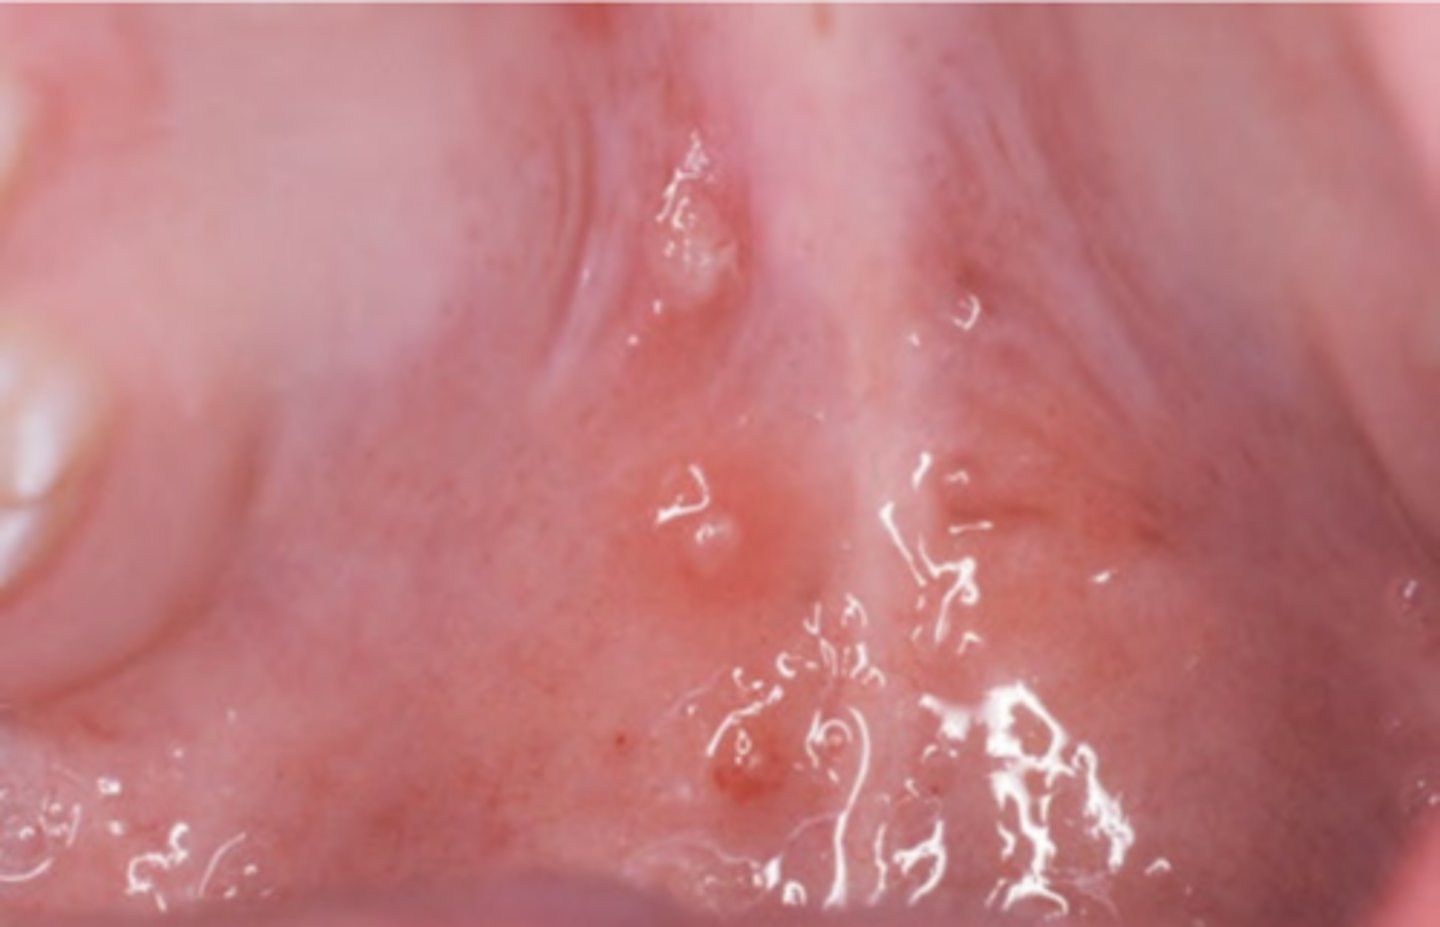

Condyloma Acuminatum

Hint: clustered, sessile, pink, well-demarcated exophytic mass with blunted surface projections